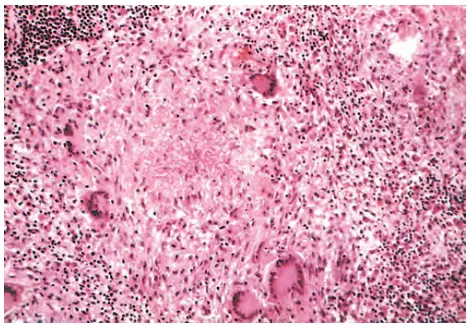

Trong các tiêu bản chế phẩm nhuộm hematoxylin và eosin thông thường, các đại thực bào hoạt hóa trong u hạt có tế bào chất có hạt, màu hồng với ranh giới tế bào không rõ ràng và được gọi là tế bào giống biểu mô (epithelioid cells) vì chúng giống với biểu mô (Hình 2). Tập hợp các đại thực bào giống biểu mô được bao quanh bởi một vòng tế bào lympho. Các u hạt cũ hơn có thể có viền nguyên bào sợi và mô liên kết. Thông thường, nhưng không phải lúc nào cũng có, các tế bào khổng lồ đa nhân có đường kính 40 đến 50 µm được tìm thấy trong u hạt; chúng được gọi là tế bào khổng lồ Langhans (Langhans giant cells). Chúng bao gồm một khối lớn tế bào chất và nhiều nhân, và chúng bắt nguồn từ sự hợp nhất của nhiều đại thực bào hoạt hóa. Trong u hạt liên quan đến một số vi sinh vật truyền nhiễm nhất định (thường gặp nhất là trực khuẩn lao), sự kết hợp giữa tình trạng thiếu oxygen và tổn thương qua trung gian gốc tự do sẽ dẫn đến vùng hoại tử trung tâm. Nhìn chung, chất này có hạt, sền sệt và do đó được gọi là hoại tử bã đậu (caseous necrosis). Về mặt hiển vi, chất hoại tử này xuất hiện dưới dạng mảnh vụn có hạt, vô định hình, không cấu trúc, ái toan, mà mất hoàn toàn các chi tiết tế bào (ngược lại với hoại tử đông, trong đó các khung tế bào được bảo tồn). Các u hạt trong bệnh Crohn, sarcoidosis và phản ứng với dị vật có xu hướng không có các trung tâm hoại tử và được cho là không hoại tử. Việc chữa lành u hạt đi kèm với xơ hóa có thể lan rộng ở các cơ quan liên quan.